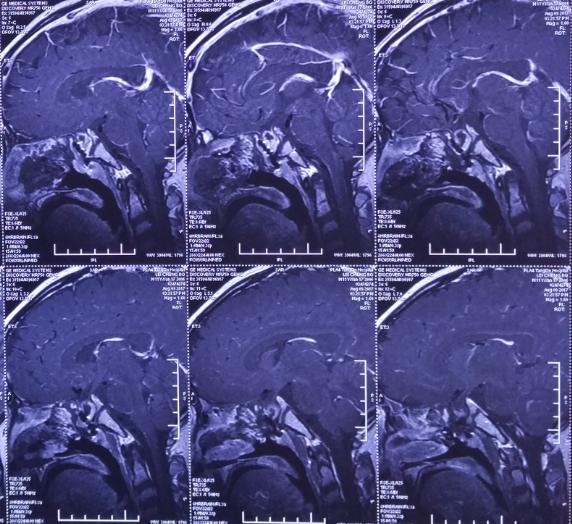

术后影像